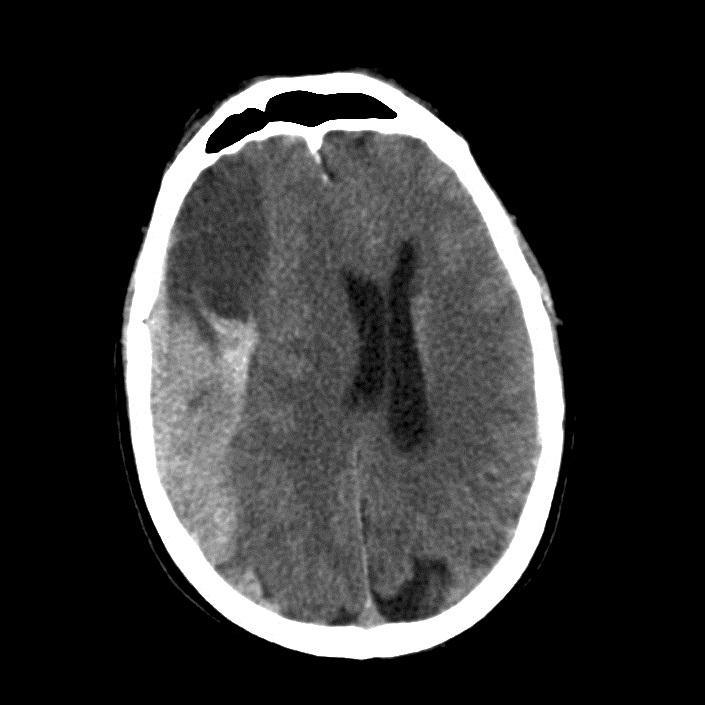

Chronic Subdural Haemorrhage